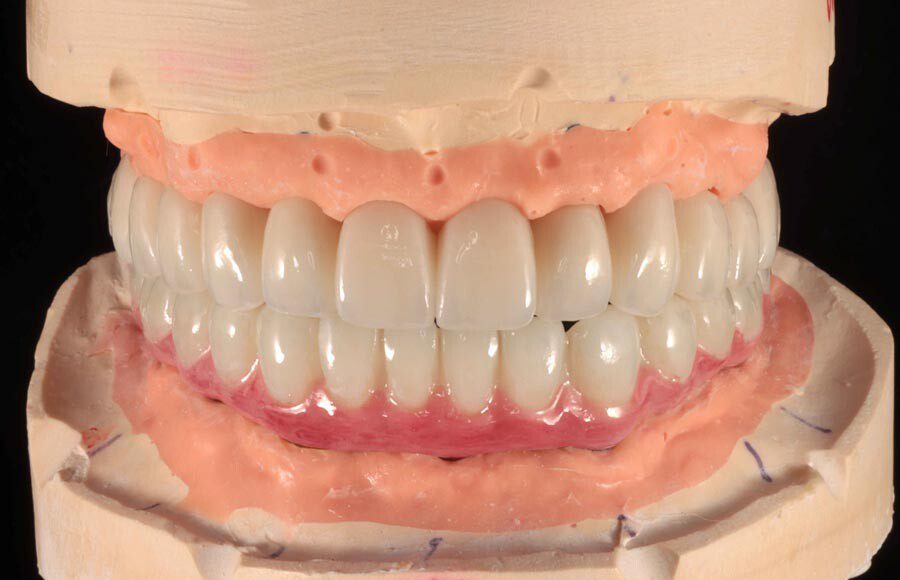

Prototype wax-up, frontal. Any imperfections or patient requests are changed in this prototype stage.